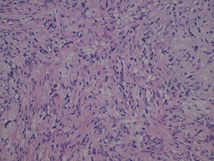

The pathological features were a multinodular proliferative lesion, composed of bland, uniform spindle-ovoid cells with no mitotic activity, in richly vascularized interstizial mixoid matrix with focal chronic inflammatory chances. The proliferative index (MIB1/Ki67) was 1%. Immunohistochemistry: neoplastic cells express smooth muscle actin. S100, H caldesmon, CD117, DOG1, CD34, SOX10, CKAE1-AE3 GFAP, MUC4, MDM2 were negative (Figures 2,3,4). Strikingly the histo-cytopathological analysis led to diagnosis of plexiform fibromyxoma.

Figure 2: Hematoxylin eosin staining